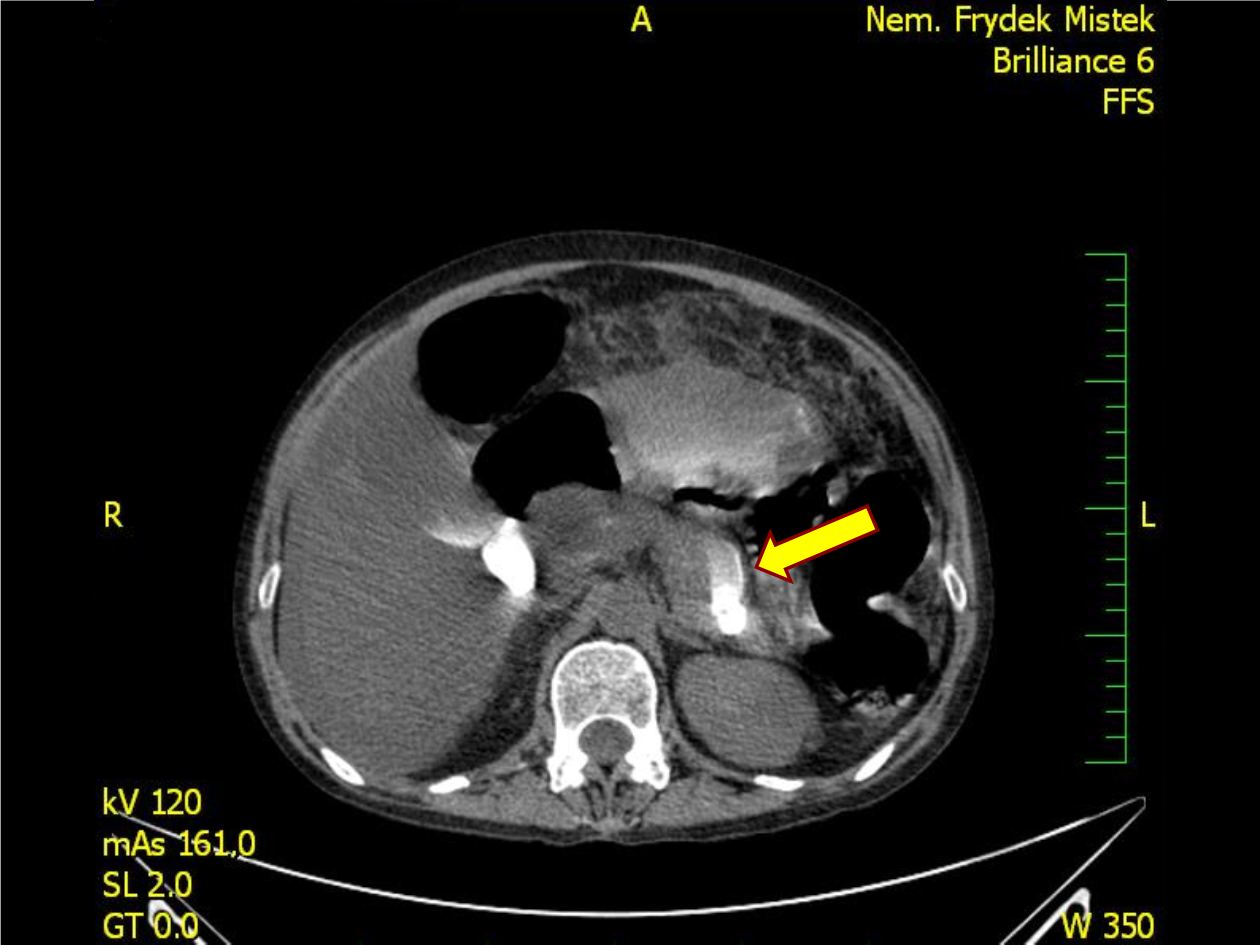

Pankreatický ascites!